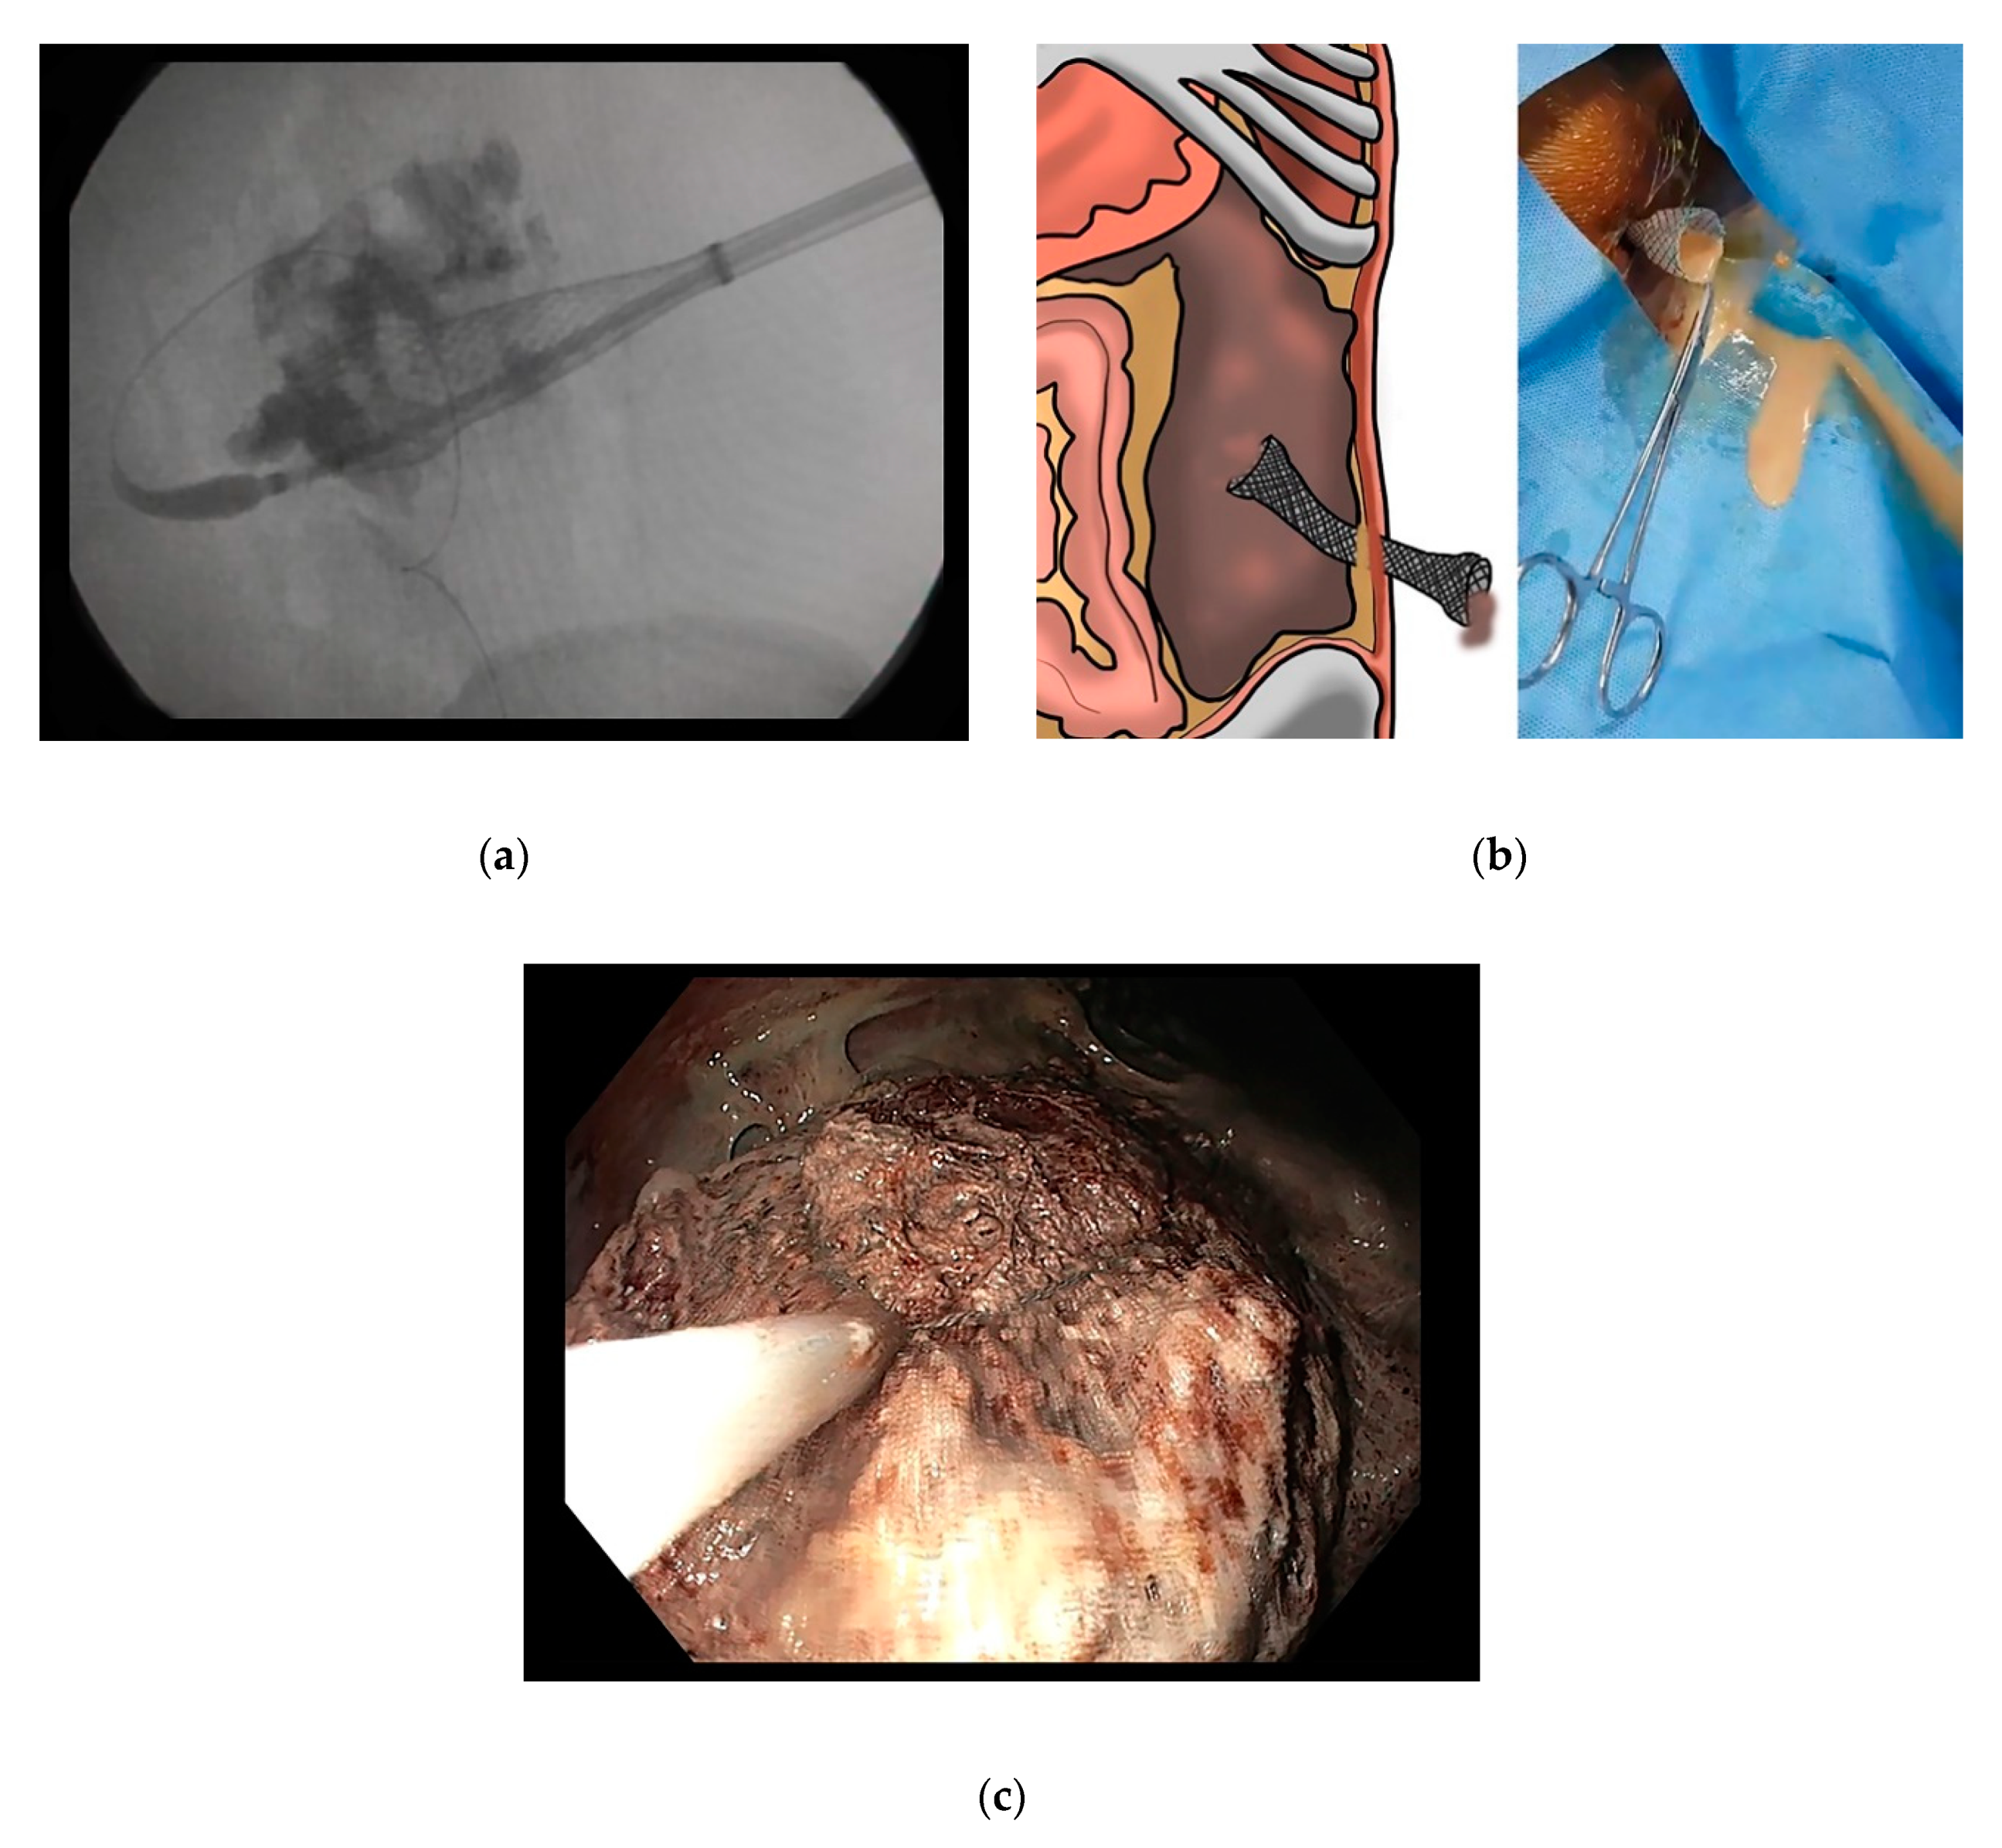

3.3.2. Percutaneous and Surgical Drainage with Step-Up Approach

4. Endoscopic Drainage